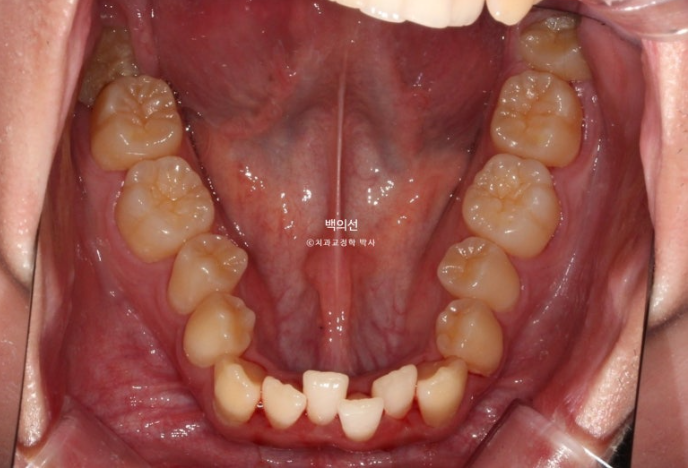

25.02

특히 아래 앞니가 많이 삐뚤하며 작은어금니가 안으로 쓰러져 있습니다.

그러나 어금니 교합관계가 1급으로 좋은 편이고 부정교합의 유형이 치아회전이 많지 않아 14개 장치 안에서 해결가능한 경미한 부정교합에 사용하는 인비절라인 라이트로 충분하여 인비절라인 라이트 권유드렸습니다.